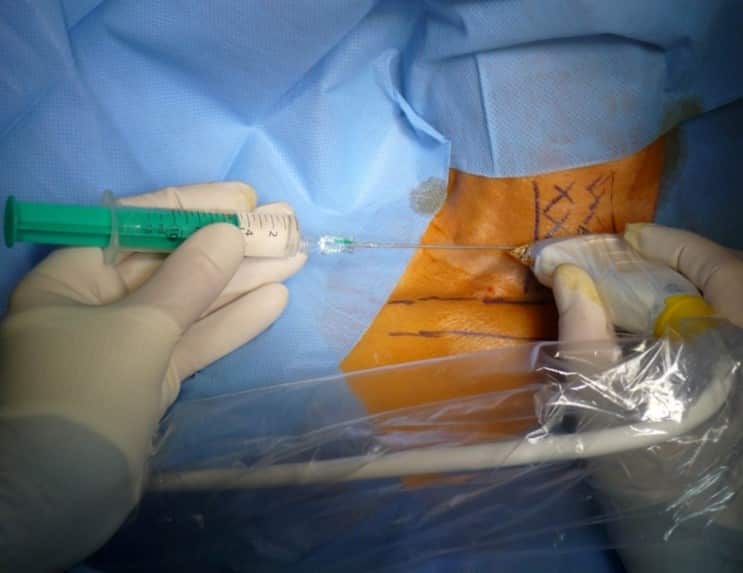

Colocación del puerto venoso

3. Acceso por la vena subclavia en adultos

La vía subclavia en comparación la vía yugular es más funcional y estética evitando muchas de las complicaciones relacionadas con la punción a ciegas.

Además, no es necesario tunelizar, es un abordaje más cómodo et rápido.

Hoy en día, nuestra vía de abordaje de elección era la vena subclavia en el surco deltopectoral, lo cual permite una gran discreción para los pacientes (respeto del escote). Colocamos el 99% de nuestros puertos con este abordaje.

En este caso, se crea el bolsillo de un tamaño ajustado al tamaño de la cámara ya que no se sutura a los tejidos subcutáneos. Eso permite que no se de la vuelta y evita las grandes dificultades que existen a la hora de la retirada cuando se sutura.

Se punciona la vena en el fondo del bolsillo: de esta manera el catéter tiene un recorrido más fisiológico y evitamos los posibles curvas o acodamientos que pueden crearse cuando la vena se punciona desde otro lugar.